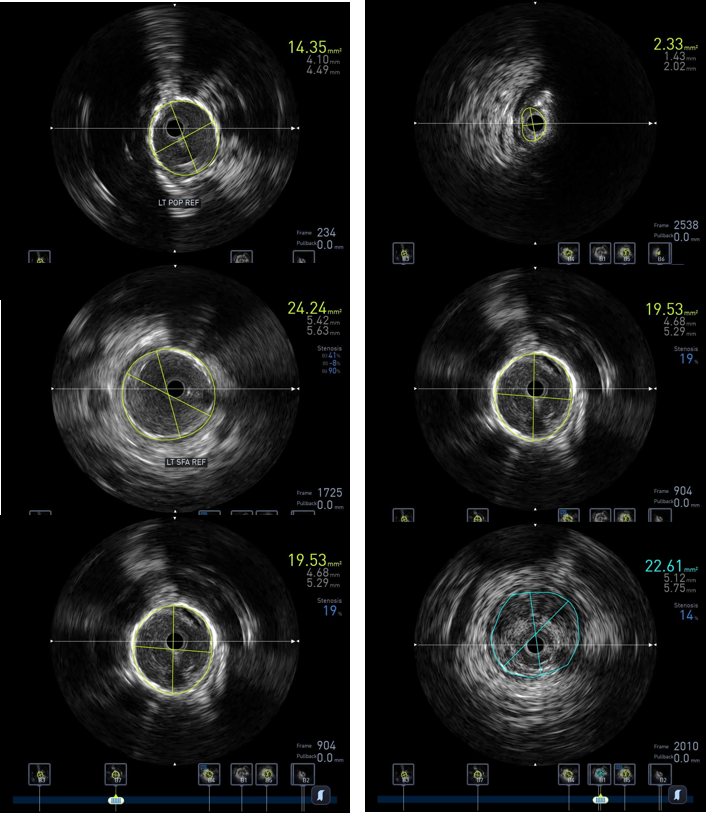

图:IVUS确认

图:IVUS测量

精准评估先行:综合运用超声、CTA、DSA,特别是IVUS,明确斑块性质(软/硬/钙化)、分布(偏心/环形)、位置(内膜/中膜)以及血栓负荷。这是所有决策的基础。

原则上真腔通过病变,最好IVUS证实。